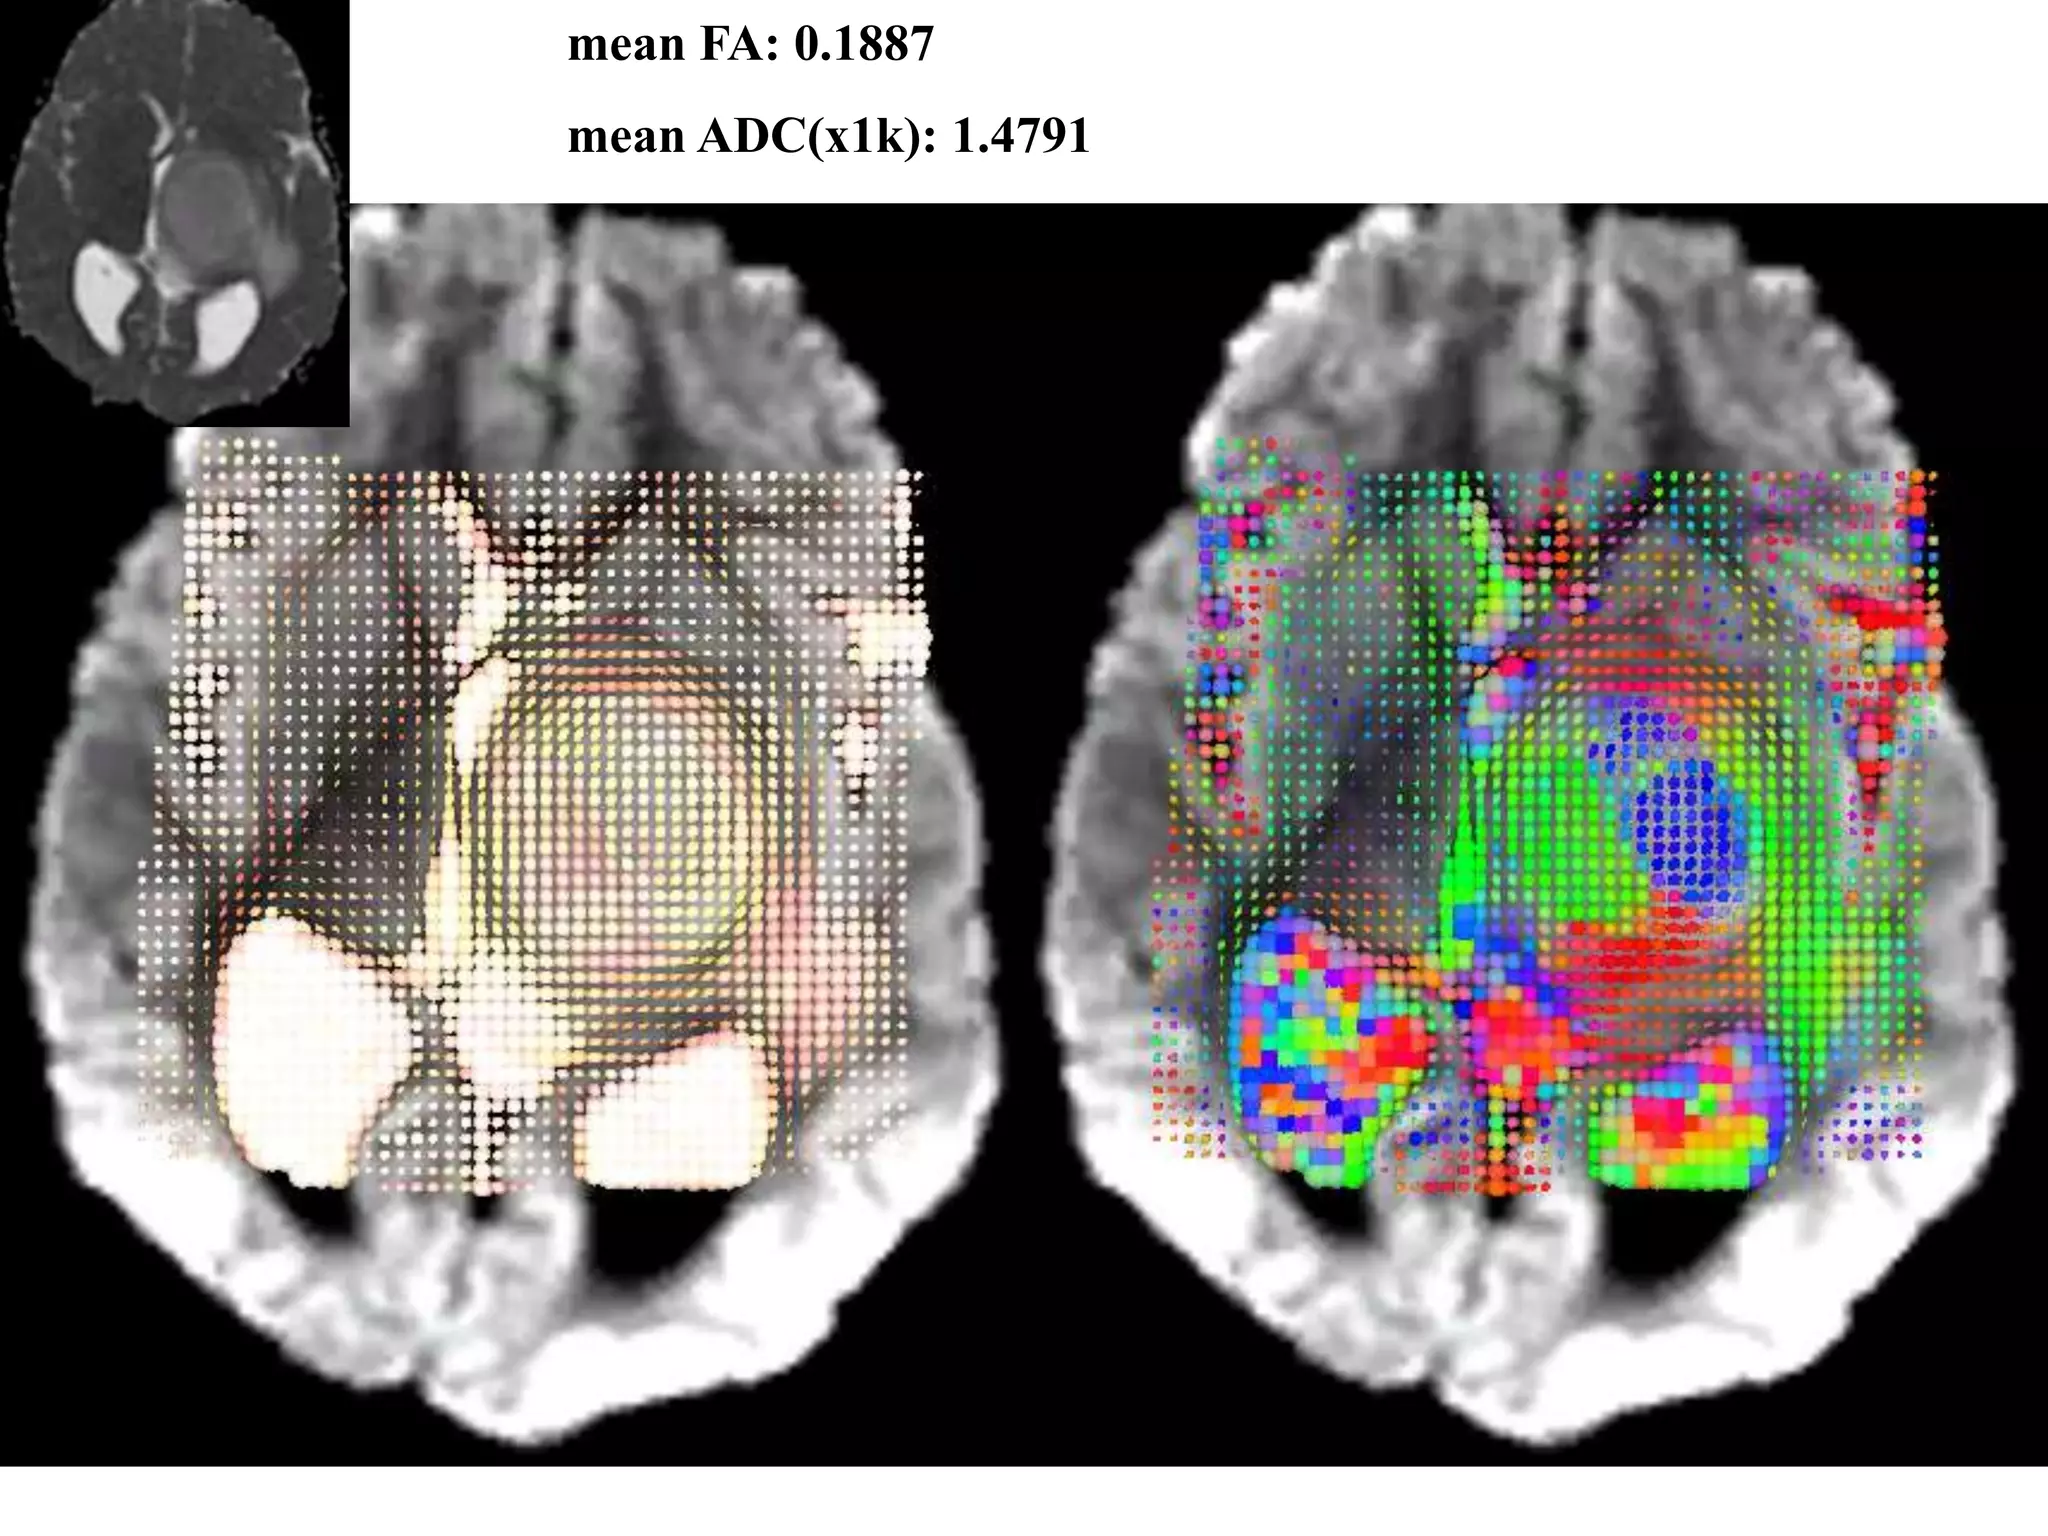

mean FA: 0.1887

mean ADC(x1k): 1.4791

DTI a neuroonkológiában

A. Jakab, M. Emri, P. Molnár, E. Berényi.

Glioma grade assessment by using

histogram analysis of diffusion tensor

imaging-derived maps. Neuroradiology.

2010 Sep 21.

Az agytumor grádusa:

Alacsony? (WHO I-II)

Magas? (WHO III-IV)

DTI a neuroonkológiában •DTI szerepe a tumorok képalkotó diagnosztikájában – FA csökkenése: fehérállomány tumoros infiltrációja / citotoxikus oedema – Tumor FA: cellularitás, proliferációs aktivitás – „current literature”: • Frakcionális anizotrópia: Cellularitás és proliferációs aktivitás (MIB-2) • MRS és DTI: Proliferációs aktivitás (Ki-67) • FA: Low grade vs. Anaplasticus glioma • ADC hisztogramok: 1p/19q l.o.h. oligodendrogliomákban • „Oligo-like” és „astro-like” komponens megjelenítése • ADC hisztogram: Terápiás válasz (Bevacizumab), progressziómentes időtartam becslése – fehérállományi képletek megjelenítése kolorizált FA képeken, ezek helyzete a tumorhoz – FEJLŐDŐ TUDOMÁNYÁG, ALAPKUTATÁS SZEREPE!

mean FA: 0.1887 meanADC(x1k): 1.4791

DTI a neuroonkológiában A.Jakab, M. Emri, P. Molnár, E. Berényi. Glioma grade assessment by using histogram analysis of diffusion tensor imaging-derived maps. Neuroradiology. 2010 Sep 21. Az agytumor grádusa: Alacsony? (WHO I-II) Magas? (WHO III-IV)